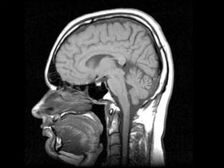

A novoszibirski tudósok kifejlesztettek egy gyógyszert, amely készíti az emberi agy az őssejtek előállításához szükséges a beteg szervek helyreállítása. “A gyógyszer a következőre vonatkozik: regeneráló, és nincs analógja a világon. Idén kezdjük klinikai vizsgálatok, preklinikai vizsgálatok, amelyeket befejeztünk “- mondta a társaság igazgatóságának elnöke és társtulajdonosa, aki kifejlesztette a gyógyszert, Andrei Artamonov. Szerinte a gyógyszer a felnőtt agyát új termelésre készteti őssejtek, amelyek később találnak egy sérült szervet, és visszaállítani. “Gyermekekben az agy aktívan termel szárot sejteket, mert a baba növekszik. És egy felnőtt agya képes előállítani őket, csak ő nem akarja ezt megtenni – neki nincs szükség. A gyógyszer serkenti a saját szár termelését sejtek “- magyarázta Artamonov. Szerinte minden operáció a Az őssejteket az emberi testen kívül termelik, amely bizonyos kockázatot hordoz azzal kapcsolatban, hogy egy módosított, mesterségesen szaporított sejt elindulhat kölcsönhatásba váratlan helyen. A cellák bevihetők, de az mindig kockázatot jelent, mert nem túl világos, hogy hol vannak differenciált. Bár ők a tiéd, szaporodnak az önön kívül testet. A saját őssejtek nem bukhatnak le ott különbséget. Megtalálják a sérült szervet, és elindítják ezt helyreállítani a testet “- tette hozzá Artamonov. Klinikai vizsgálatok a gyógyszer másfél évig fog tartani, számol be az Interfax.